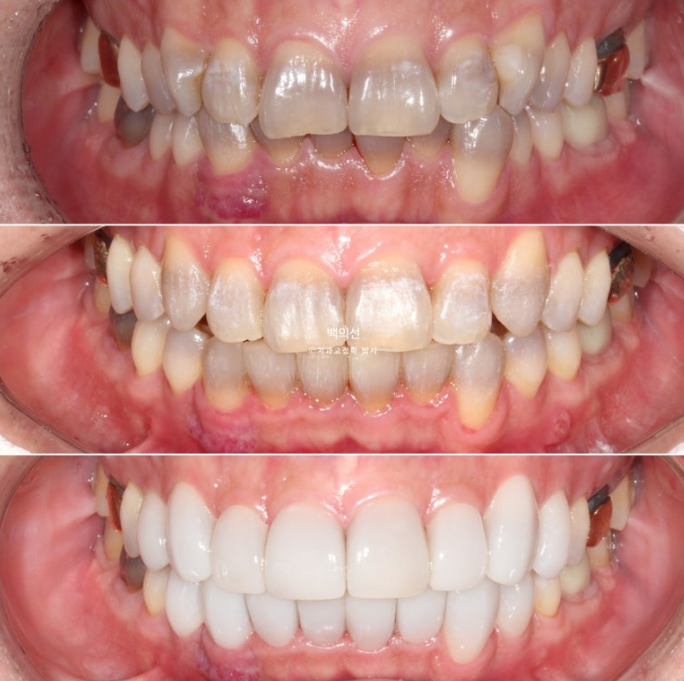

The discoloration is severe, with a fairly deep gray tone.

However, as you can see from the front, the canine crowding means laminate treatment would be difficult unless orthodontic treatment is done first.

In the lower front teeth, there are varying heights in addition to the canine crowding.

Now let’s compare the initial visit, after orthodontic treatment, and after Gelami in sequence.

No-prep laminate has to be made thin, so the original tooth color inevitably shows through to some extent. In the facial photo, it can be seen that the original dark gray tooth color is showing through.

The way to prevent this gray tone from showing through is to remove some tooth structure and make the laminate thicker.

However, the patient wanted a no-prep approach, so we decided to accept some degree of gray tone.